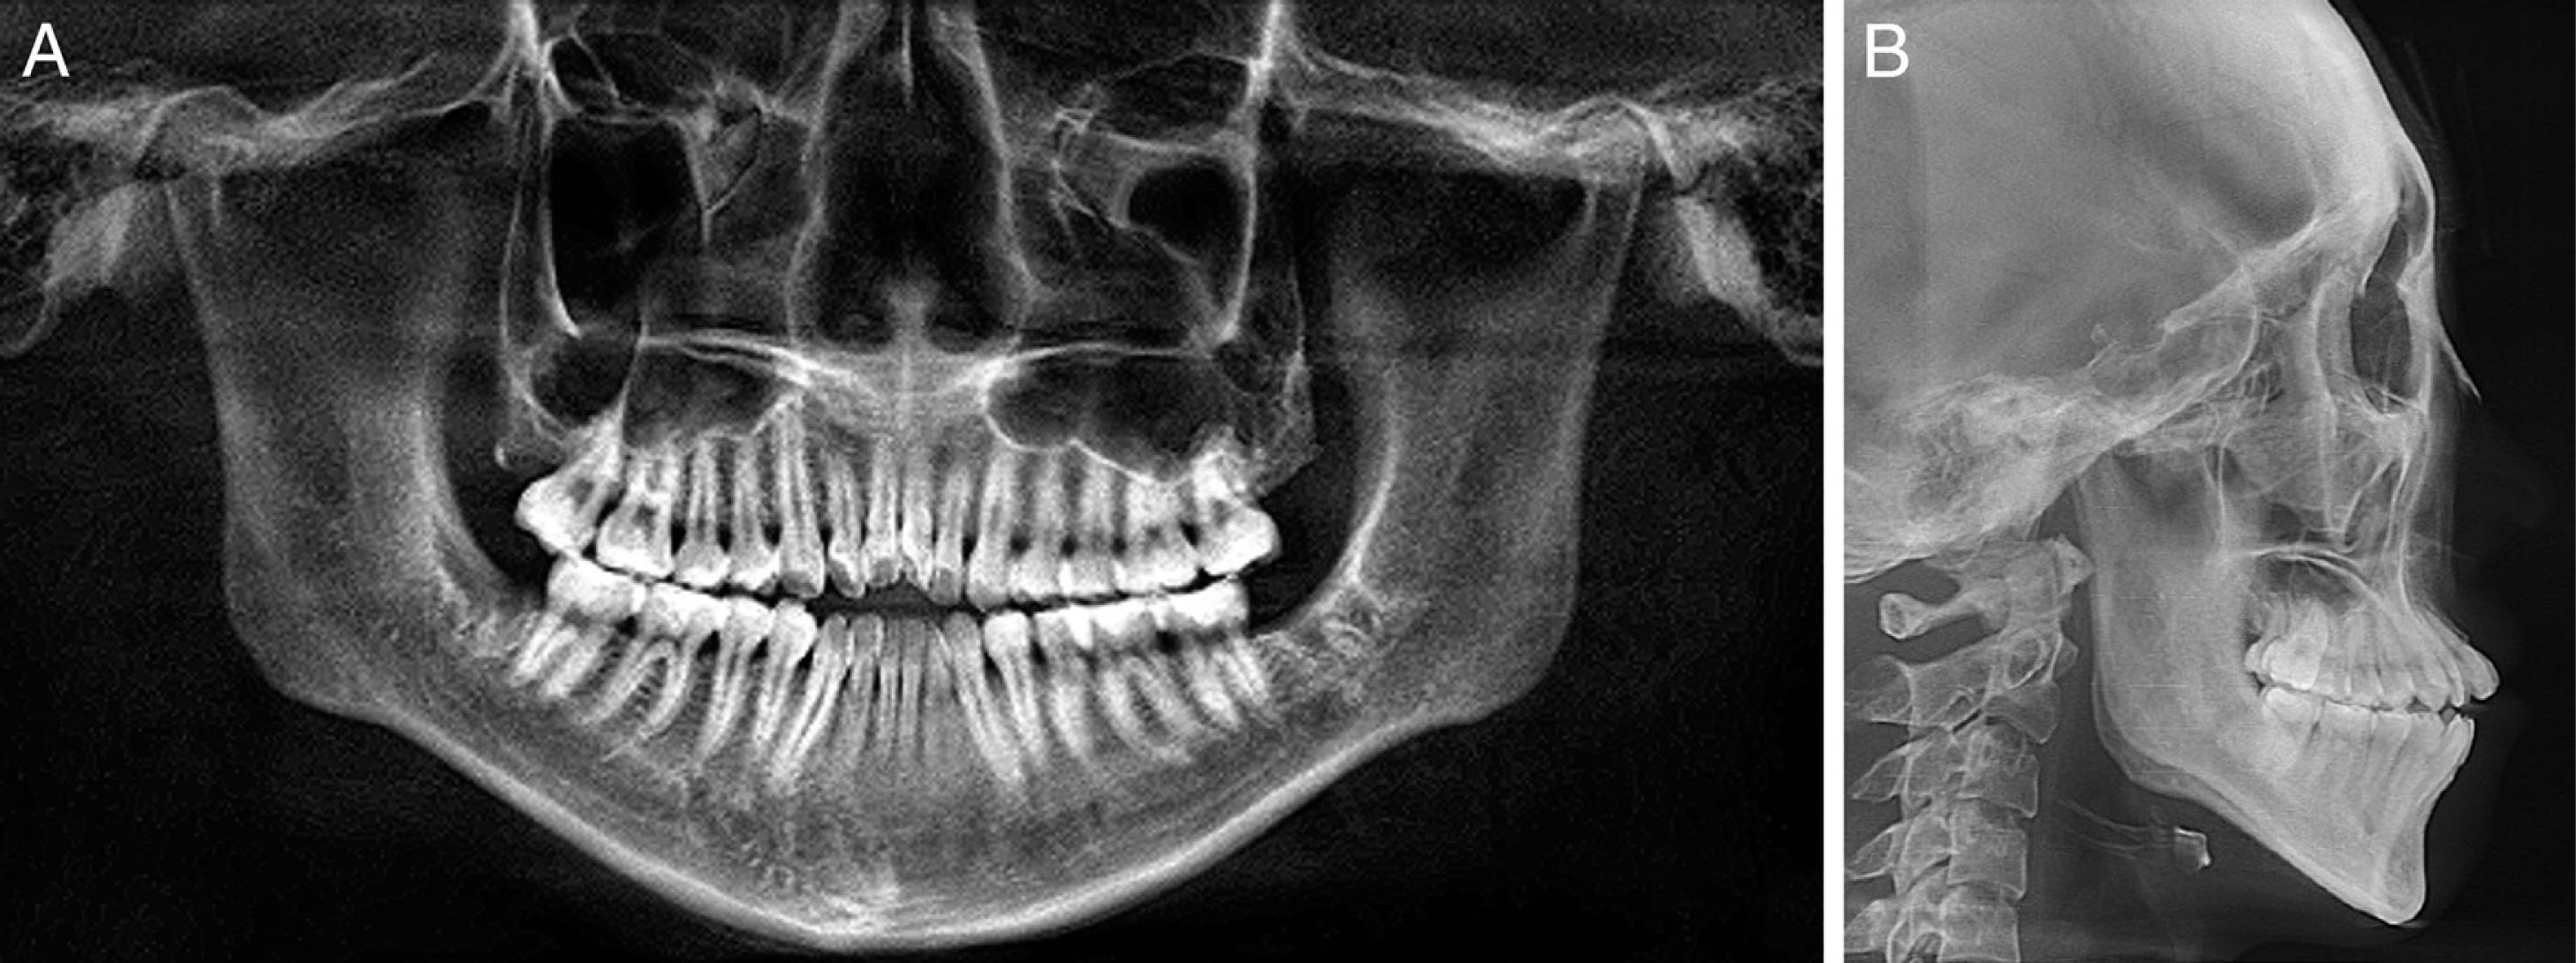

A 24-year-old female patient presented with a history of tongue thrust and mouth breathing but without a history of maxillofacial trauma or a non-nutritive sucking habit. The diagnostic records revealed that, based on the E line, the patient had a convex profile with a long face, a decreased nasolabial angle, a protrusive lower lip, and a shallow mentolabial sulcus. Further, the patient had incompetent and protruded lips at rest and in contact but with mentalis strain upon forcible closure. There was also a low smile line, and the smile arc was not consonant with the curvature of the lower lip (Figure 1). An intraoral examination showed an anterior open bite with no occlusal contact from the right first premolar to the left first premolar, a bilateral Class III molar relationship, and a Class III canine relationship on the right side but a Class I relationship on the left side. An analysis of the initial study models revealed that there was an anterior dental open bite of 6 mm, a decreased overjet (the overjet and overbite were measured on digital dental models using 3-shape software), a 3 mm curve of Spee, a mandibular midline deviation (1.5 mm to the left), and arch-length discrepancies of 5 mm in the maxilla and 3 mm in the mandible. The anterior and overall Bolton ratios were compatible. The maxillary dental arch was narrow, and the upper and lower arches were unmatched. A crossbite from the upper left canine to the second premolar was also noted during the examination. The maxillary right second molar was in scissor-bite with the mandibular right second molar (Figure 2). A cephalometric analysis revealed a skeletal open bite (SN/GO-GN 48°), an increased mandibular plane angle, a counter-clockwise rotation of the ANS-PNS plane (S-N/ANS-PNS 6°), proclination of the upper incisors (UI/ANS-PNS 129°), an interincisal angle of 108°, excessive lower anterior facial height and a short upper anterior facial height (Table I). A computed tomography scan of the anterior teeth revealed adequate labial and lingual bone volumes (Figure 3A). In addition, the initial panoramic radiograph and the radiographic and clinical examinations of the temporomandibular joints revealed no obvious abnormalities (Figure 4 and 3B). The patient was diagnosed with a Class III malocclusion (S-N/ANS-PNS 6°) and skeletal open bite (SN/GO-GN 48°) with an increased mandibular plane angle, a long face, a convex profile, and lip incompetence with mentalis strain. There was also proclination of the upper incisors, a crossbite, scissor-bite, mild crowding and midline deviation.

Pre-treatment panoramic radiograph (A) and lateral cephalometric radiograph (B).